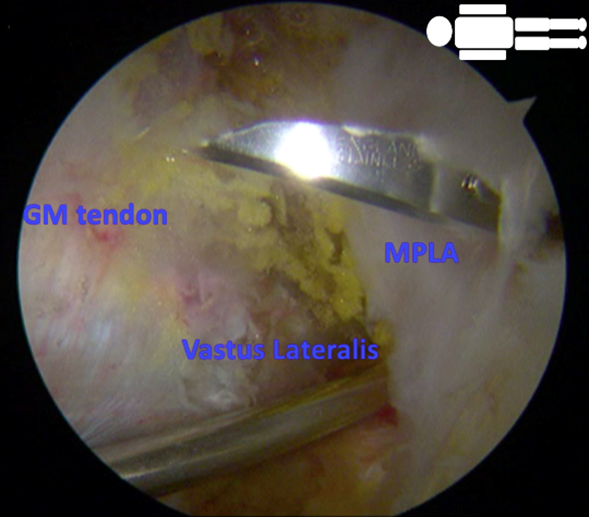

To perform a DPLA portal, a small incision is made in the skin, followed by an opening in the iliotibial band. To avoid the risk of hypothermia, a warmed physiological solution is used during the procedure.26–28 Using endoscopic assistance with 70º optics, a second portal, the PPLA, is made, with a constant flow at a rate of 0.7 liters/minute and a pressure of 40mmHg per bomb. The procedure starts with the hip at a 30º abduction and 0º internal rotation. Then, a partial tenotomy of the distal insertion of the gluteus maximus is performed. The tenotomy is done at the proximal level on the linea aspera, in an anterior-to-posterior direction Figure 2. The tenotomy procedure increases the virtual space available, allowing complete access and reducing pressure on the lateral space. After identifying the greater trochanter, a bursectomy is performed to locate the GM tendon. The tendon shows partial fatty infiltration and tendinopathic appearance on its lateral surface but without tears Figure 3.

Tears are always found on the medial side, which cannot be directly observed. It is explored by palpation to rule out a complete rupture. A third portal is made at the midpoint equidistant between the PPLA and DPLA, the medium posterolateral accessory (MPLA) portal Figure 4. Through this MPLA portal, nine perforations are made in the greater trochanter at the level of the GM insertion with a 2.3mm Bioraptor® anchor drill bit (Smith & Nephew, London, United Kingdom) at a depth of 2.5cm, distributed symmetrically separated approximately 1cm from each other Figure 5. Through the DPLA portal, an 8.25mm cannula specific to the implant is inserted, and then the Regeneten® bioinductive patch loaded is passed. Once the implant has been placed in the desired position, 6 anchors of the Regeneten® system for soft tissues (4.5x6.5mm) are placed through the MPLA portal to set the patch Figure 6. Subsequently, the stability of the implant is confirmed by hip rotation and flexion-extension movements Figure 7. Instruments are removed and the skin is sutured, concluding the surgical procedure.

Figure 4 Realization of the medium posterolateral accessory (MPLA) portal, equidistant to the PPLA and DPLA portals.